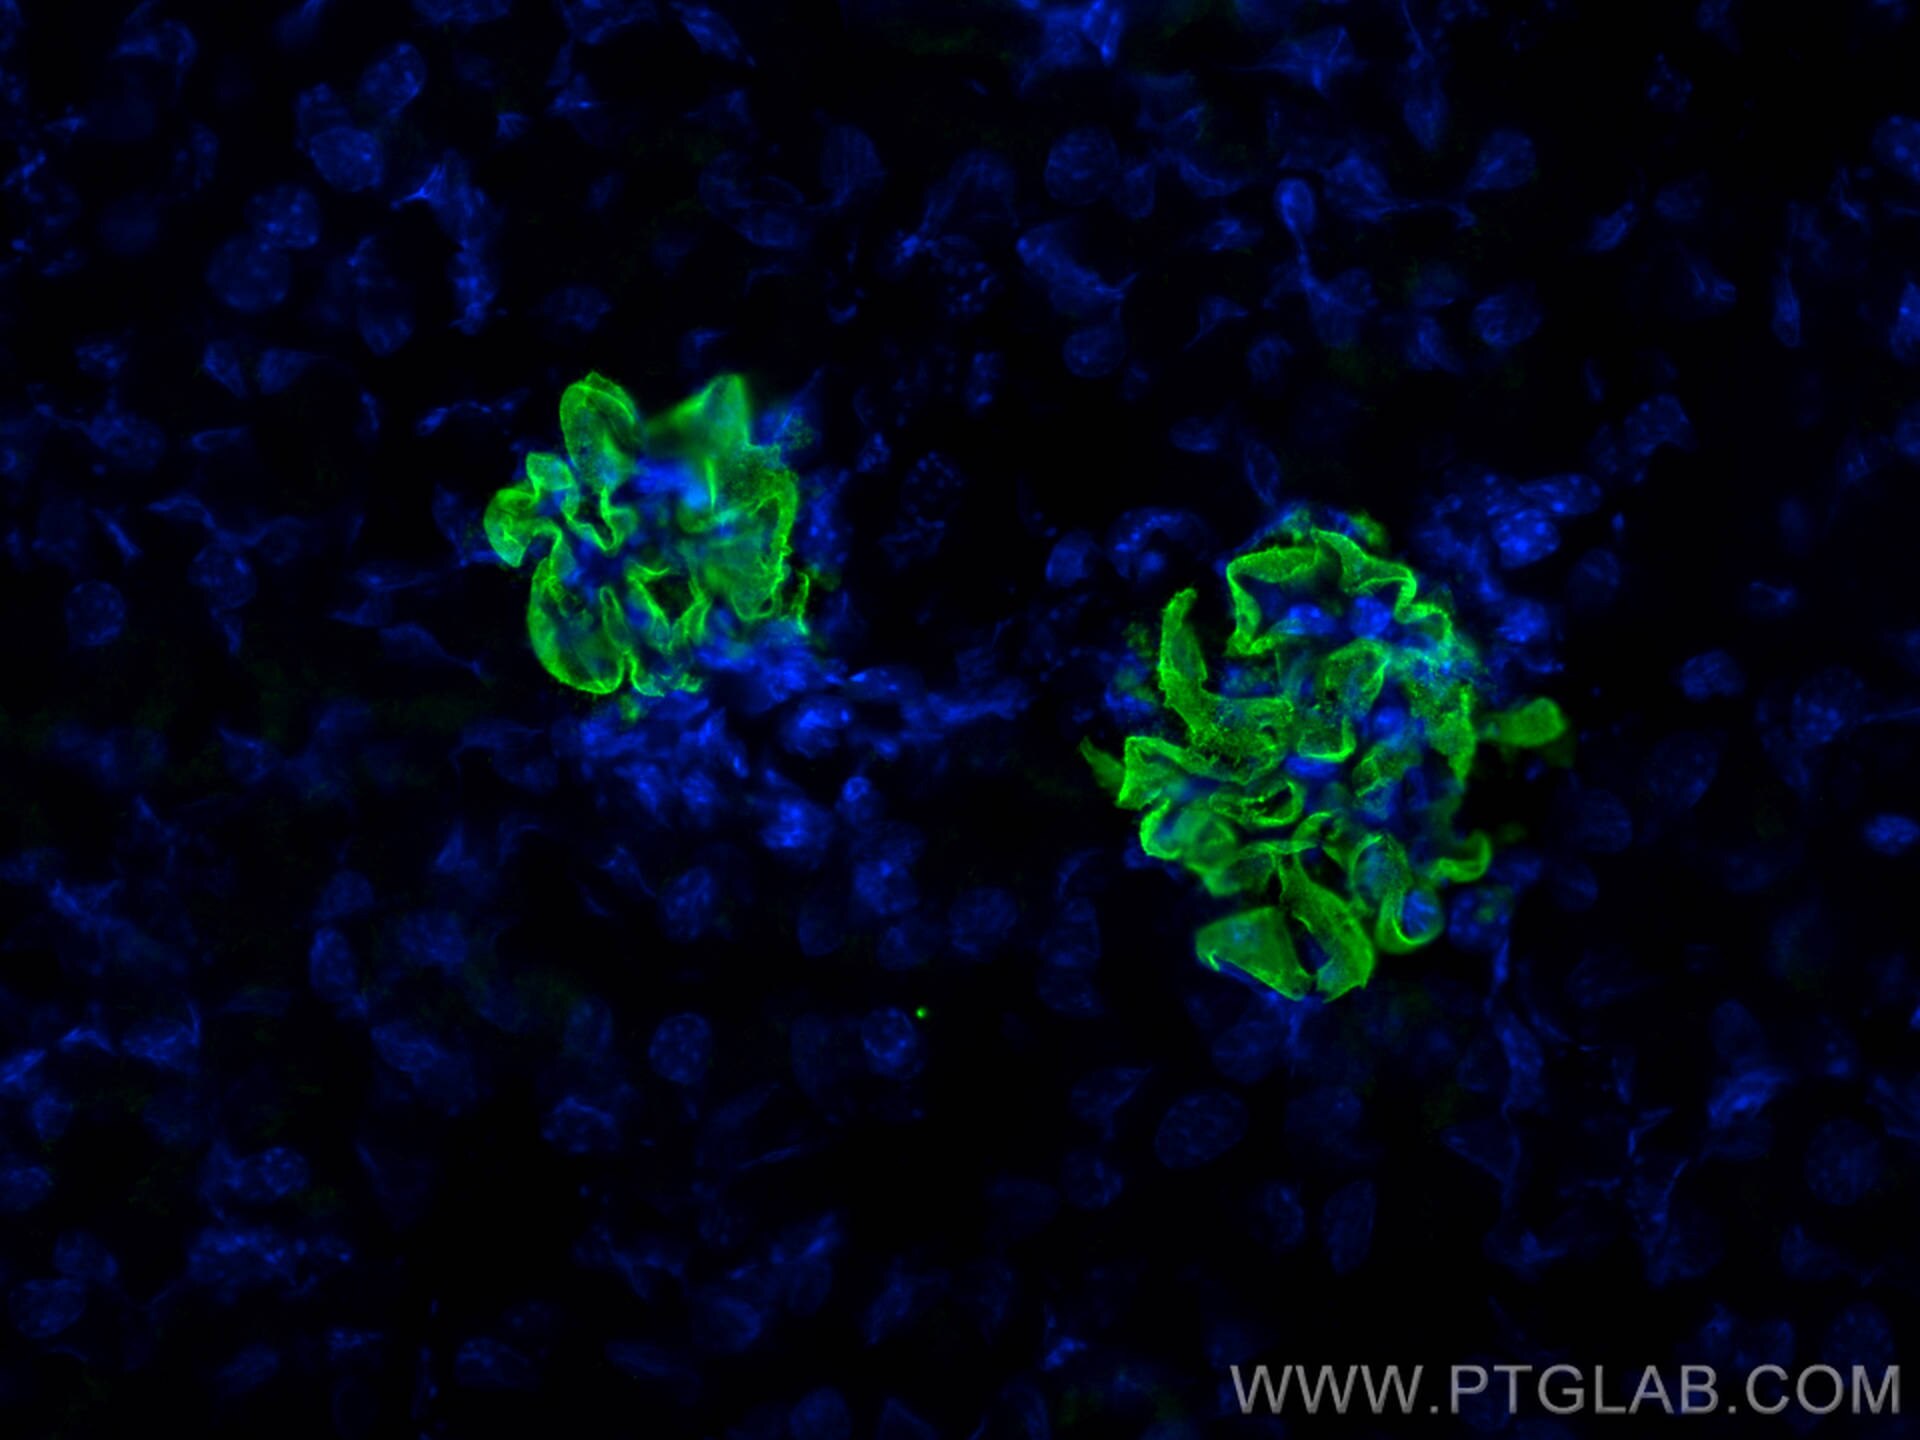

| Positive IF detected in | mouse kidney tissue, zebrafish embryos |

NPHS2 (also known as Podocin) is a membrane protein located on the podocyte foot process and is the critical component of the glomerular filtration barrier. Mutations of NPHS2 cause recessive steroidresistant nephrotic syndrome. Two isoforms of NPHS2 exist with molecular weights of 42 kDa and 35 kDa, respectively. (PMID: 21499232)